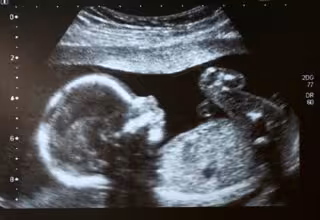

Archivo - Ecografía. Feto. Embarazo.

Archivo - Ecografía. Feto. Embarazo. - ISTOCK - Archivo